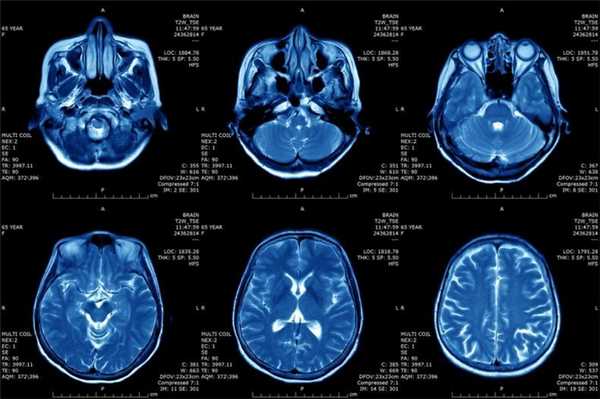

- Томография. Для определения стадии заболевания и получения более полных данных о структуре, размере и расположении фибросаркомы при необходимости назначают КТ и МРТ.

Магнитно-резонансная томография или МРТ - это сфокусированный метод, который проводит очень детальное обследование. Диагностическая точность МРТ превышает УЗИ и во многих случаях КТ, за исключением сканирования полых органов (легких, желудка, кишечника) и костей. МРТ является золотым стандартом диагностики:

- заболеваний головного и спинного мозга;

Принцип работы МРТ основан на эффекте ядерного магнитного резонанса. МР томограф в своей конструкции имеет мощный магнит, который создает магнитное поле, и датчик, который подает радиочастотные сигналы. В такой ситуации протоны атомов водорода начинают колебательные движения, выделяя при этом импульсы. Их улавливает компьютер томографа и преобразовывает в трехмерные изображения. Чем больше воды содержится в клетках ткани, тем детальней получается ее изображение. Поэтому на МРТ хорошо отображаются органы с большим содержанием воды: МРТ головного мозга, МРТ спинного мозга, МРТ глазных орбит, МРТ органов малого таза, МРТ позвоночника, МРТ суставов, и плохо визуализируются органы с большим содержанием воздуха МРТ органов грудной клетки или кости.

МРТ будет эффективно при исследовании опухолей, мозга и аномалиях развития сосудов.

Магнитно-резонансная томография

В основе МРТ лежит явление магнитного резонанса, основанного на переизлучении радиоволн, взаимодействующих с атомами водорода, в избытке содержащимися в организме человека. Эти переизлученные электромагнитные волны улавливаются датчиком МР-томографа, усиливаются и в виде цифровых изображений появляются на экране монитора. Это безвредный и абсолютно безопасный для здоровья человека метод лучевой диагностики, так как в основе получения изображения отсутствует рентгеновское излучение, поэтому МРТ можно проходить неограниченное количество раз, с любым интервалом.

Существенное преимущество МР-томографии перед КТ заключается в том, что она не противопоказана беременным во II и III триместре и совершенно безопасна для детей. В МРТ исследуемая область сканируется в трех проекциях, что позволяет врачу-рентгенологу в полной мере оценить состояние тканей и органов исследуемой области, а высокая контрастность изображения и пространственное разрешение позволяют визуализировать серое и белое вещество головного мозга, оценивать состояние костного мозга и мягких тканей различной локализации. Кроме того, метод МРТ позволяет получать изображения сосудов головного мозга и сосудов шеи без введения контрастного препарата.

Мы также всегда делаем КТ пациентам с подозрением на нарушение мозгового кровообращения, исследование позволяет не только подтвердить диагноз, но и оценить «масштаб» поражения и выработать верную тактику. Назначают его при патологии почек, в частности, при наличии камней. На томографе можно увидеть их расположение, оценить плотность и структуру, а значит, принять решение об операции или выборе консервативных методов. МРТ имеет преимущества при изучении патологий суставов, для диагностики заболеваний головного мозга, спинного мозга, органов малого таза.